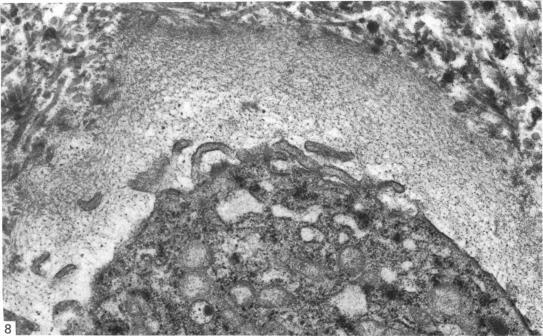

Normal human menisci obtained at autopsy (seven cases) and the injured and uninjured portions of torn menisci obtained at surgery (nine cases) were studied with the electron microscope. The surface of menisci is composed of collagen fibrils surmounted by an electron-dense surface coat. Most of the cells in menisci are chondrocytes but a few fibroblasts and cells of an intermediate form difficult to classify as either fibroblasts or chondrocytes also occur. Mast cells are found at the vascularised periphery of the meniscus. Myofibroblasts were found in the injured portions of menisci in three out of the nine cases studied. A territorial matrix containing fibrils and proteoglycan particles with associated filaments is seen around or adjacent to chondrocytes, but sometimes this matrix is sparse or absent. The interterritorial or general matrix comprises collagen fibrils of widely varying diameters (25-180 nm) set in a sparse interfibrillary matrix containing proteoglycan particles. A few mature elastic fibres and several small or immature elastic fibres and collections of electron-dense filaments are seen in the general matrix. Also seen in this region are calcified bodies and matrical lipidic debris derived by the shedding of cell processes and in situ necrosis of cells. Other features seen in the matrix of the injured portion of the meniscus include: (1) membrane-bound cystic structures; (2) parting and fraying of collagen fibrils; and (3) pools of proteoglycan particles.

对尸检获得的正常人类半月板(7例)以及手术中获得的撕裂半月板的损伤和未损伤部分(9例)进行了电子显微镜研究。半月板表面由胶原纤维组成,其上方有一层电子致密的表面涂层。半月板中的大多数细胞是软骨细胞,但也有一些成纤维细胞以及难以归类为成纤维细胞或软骨细胞的中间形态细胞。在半月板血管化的周边发现了肥大细胞。在所研究的9例中,有3例在半月板的损伤部分发现了肌成纤维细胞。在软骨细胞周围或附近可见到一个含纤维和蛋白聚糖颗粒以及相关细丝的区域基质,但有时这种基质稀疏或不存在。区域间或一般基质由直径差异很大(25 - 180纳米)的胶原纤维组成,这些纤维分布在含有蛋白聚糖颗粒的稀疏纤维间基质中。在一般基质中可见到一些成熟的弹性纤维、几条小的或不成熟的弹性纤维以及电子致密细丝的聚集物。在该区域还可见到钙化小体以及由细胞突起脱落和细胞原位坏死产生的基质脂质碎片。在半月板损伤部分的基质中还可见到其他特征:(1)膜结合的囊性结构;(2)胶原纤维的分离和磨损;(3)蛋白聚糖颗粒池。